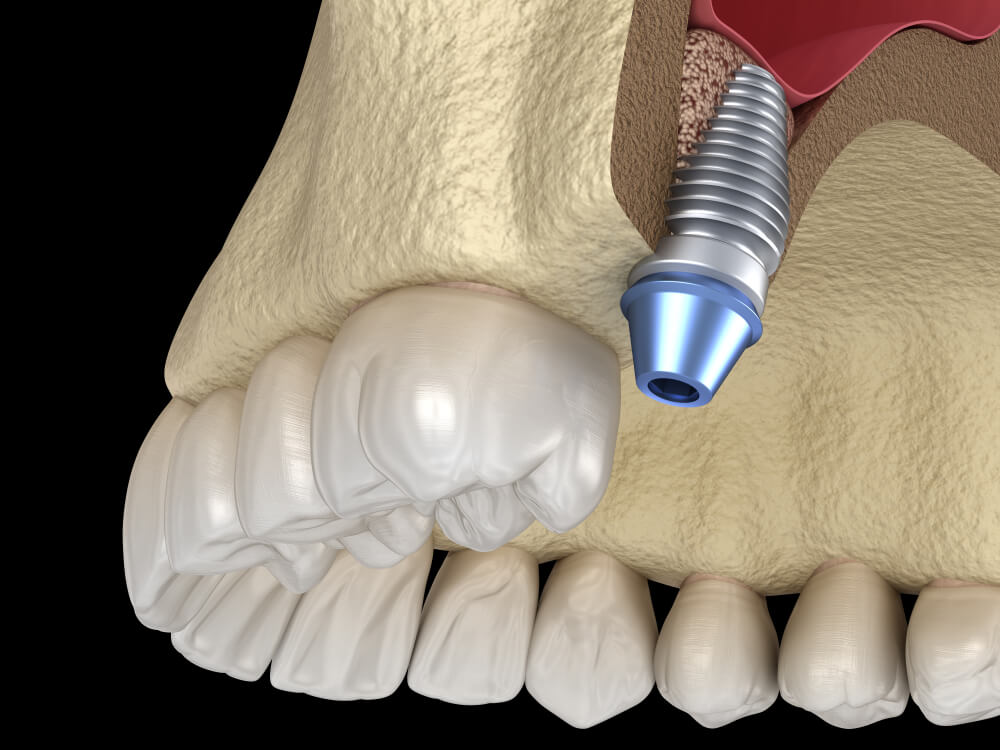

Zubni impanti

Zubni implanti su i dalje jedan od najnaprednijih dostignuća u oblasti stomatologije. Idealna su alternativa kada je u pitanju nadoknada jednog ili više zuba.

Kada nema dovoljno kosti u gornjoj vilici u koju bi trebalo ušrafiti zubni implant, stomatolozi procenjuju da treba uraditi dogradnju kosti.

Svi znamo da su sinusi zapravo šupljine koje se nalaze iznad gornje vilice, oko nosa i očiju. Ukoliko vam nedostaju zubi u predelu zadnje gornje vilične kosti, trebaće vam dovoljno te iste kosti kako bi držala implant. U suprotnom implant neće imati dovoljnu stabilnost koja je potrebna za podupiranje vašeg novog, životnog nosača zuba i zubnih krunica.

Veličina kosti koja se ugrađuje varira u zavisnosti od dubine implanta, ali je u pitanju nekoliko milimetara iznad vilice.